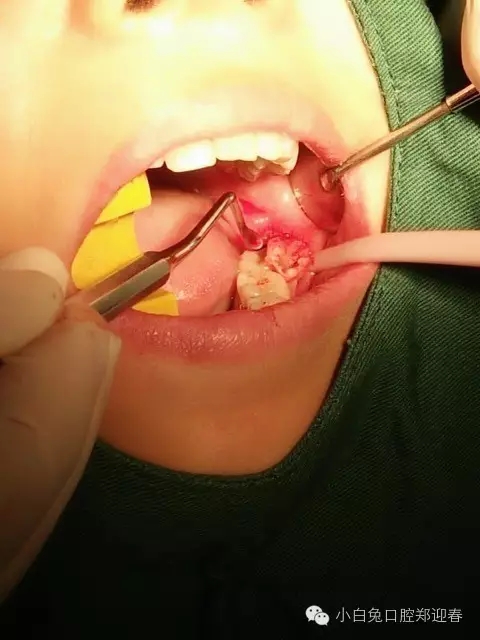

使用微創(chuàng)理念及方法繼續(xù)拔除剩余部分

一例智齒斷根進行二次拔除的感悟